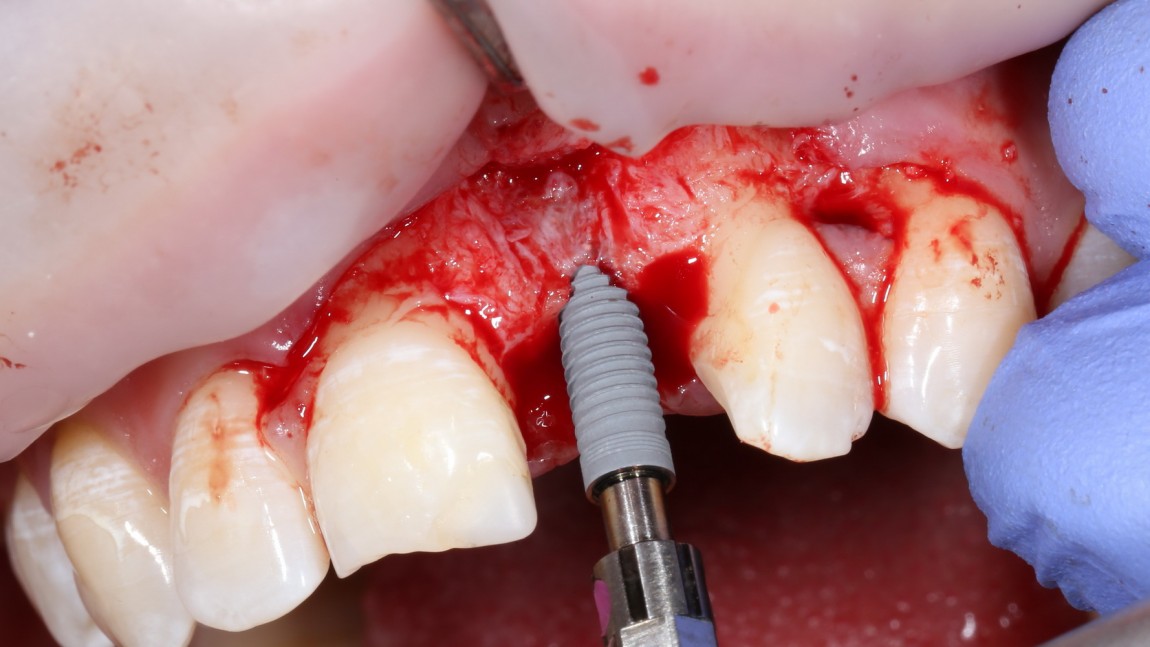

Это Nobel Replace CC 3.5×13 mm. Оптимальный размер импланта для работы в этом клиническом случае.

И вот, как я вам уже говорил, Nobel — не такая простая система, как может показаться на первый взгляд. Самая большая сложность — выдержать и не превысить нужный крутящий момент при установке импланта. По предлагаемому производителем протоколу, крутящий момент при установке Replace — где-то до 40 НМ. По факту, из-за особенностей макродизайна, торк при установке легко превысить — даже в III или IV биотипе костной ткани (т. н. «очень рыхлая кость») получается за 70 НМ и выше. Чем грозят такие усилия при установке импланта, по-моему, объяснять не нужно: излишнее давление на костную ткань, ишемия, некроз, а далее — в лучшем случае, периимплантит, в худшем — отторжение. Поэтому, если у вас не получается установить имплантат при крутящем моменте до 40 НМ (неважно, с немедленной нагрузкой или нет), я рекомендую вытащить его, заново пройти и чуть-чуть перерасширить лунку, а затем повторить установку. НЕЛЬЗЯ ПРИКЛАДЫВАТЬ ЧРЕЗМЕРНЫЕ УСИЛИЯ ПРИ УСТАНОВКЕ ИМПЛАНТОВ. Сильно не рекомендую пользоваться входящим в комплект динанометрическим ключом, поскольку при его использовании усилия становятся совсем уж неконтролируемыми. Соблюдая это правило, вы со временем вообще забудете, что такое периимплантиты и отторжения.

Продолжим нашу работу. Имплантат установлен:

Работа закончена? Отнюдь, нет. Теперь наша задача — восстановить утраченные объемы костной ткани вокруг импланта. Ибо, как вы видите на фото, его вестибулярная поверхность, практически, просвечивает. И, если ничего не делать, дальше будет только хуже.